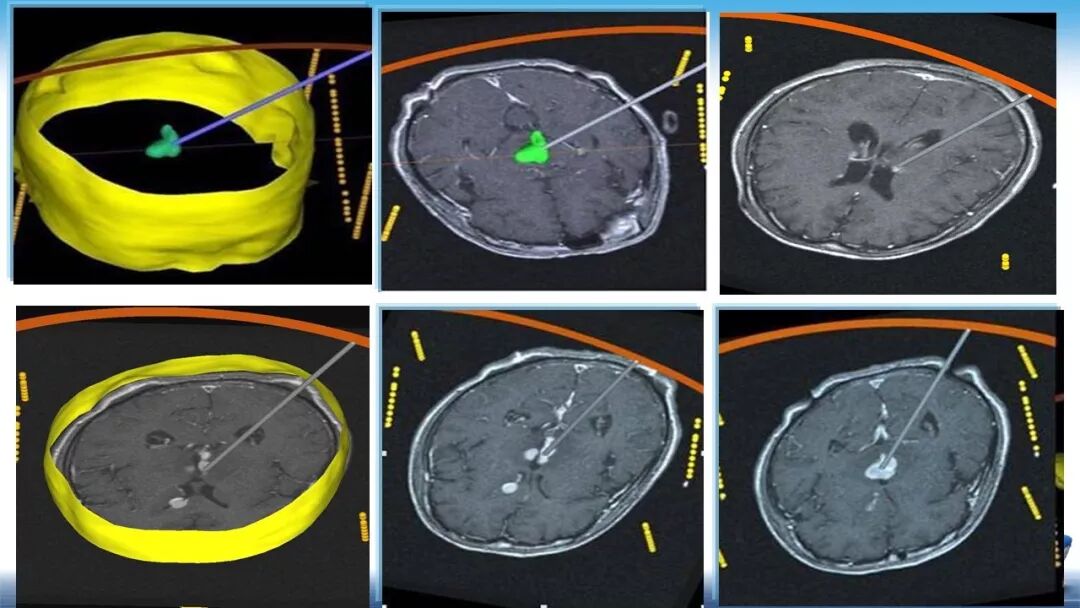

立体定向活检在脑干中线病变精准诊断中的作用

今天为大家带来的是中国人民解放军总医院第六医学中心(原中国人民解放军海军总医院)王亚明、于新、张剑宁带来的精彩课题分享:立体定向活检在脑干中线病变精准诊断中的作用,欢迎观看、阅读!